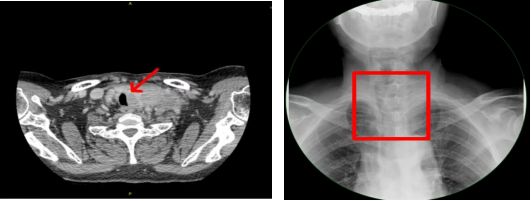

颈部增强CT图像:气管受压右移;食管X线造影图像:食管受压右移,管腔狭窄